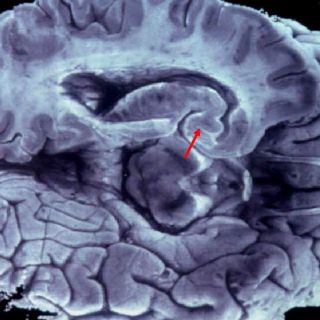

Los exámenes permiten ubicar al péptido beta-amyloid, fundamental en el desarrollo de esta afección que entre otros síntomas incluye demencia, pérdida de memoria y declive cognocitivo.

Se estima posible que cuando se perfeccionen y salga al mercado este tipo de pruebas, se podrá prescindir del escaneo cerebral o los análisis de fluido espinal, que son los preocedimientos actuales de detección del mal.